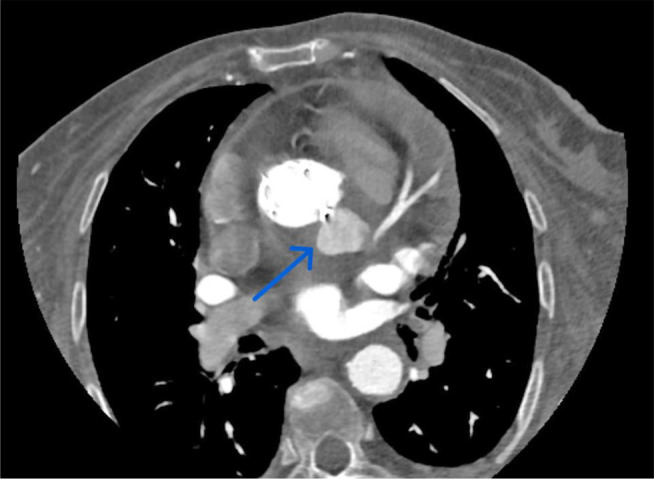

Surgical approach to complicated transcatheter aortic valve implantation endocarditis.